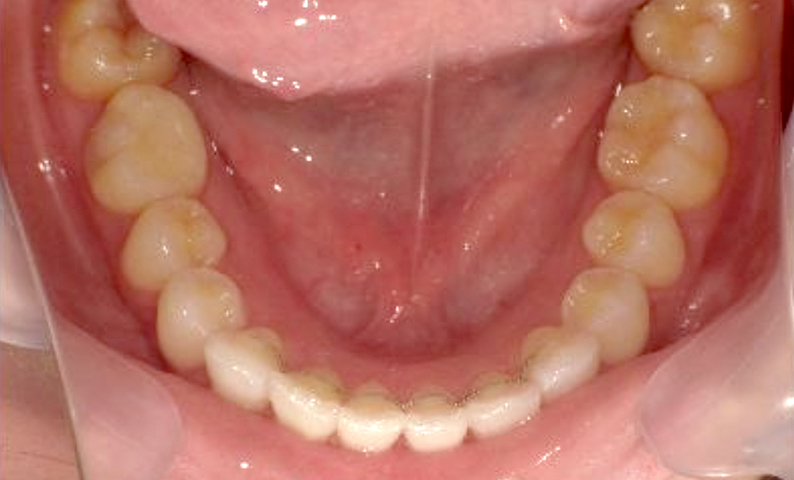

症例_001 下顎だけの部分矯正

治療期間:6ヶ月金額:27万円+税女性前歯のガタガタ下の前歯だけ

| Before | After |

|---|---|

|